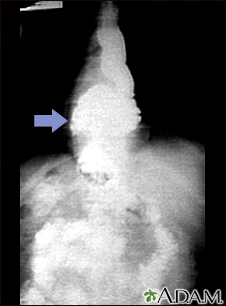

Hiatal hernia - x-ray